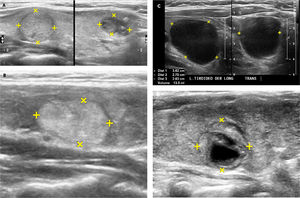

Nódulos tiroideos.

A: A la izquierda un nódulo tiroideo sólido, isoecogénico (igual ecogenicidad que el resto del lóbulo) y a la derecha la imagen de un nódulo hipoecogénico (más oscuro que el resto del tejido tiroideo normal circundante), en este caso con algunas calcificaciones gruesas (imágenes blancas de ubicación excéntrica, superiores derechas).

B: Corte ecográfico longitudinal de un nódulo tiroideo (entre las cruces): sólido, hiperecogénico, bien delimitado, sin calcificaciones.

C: Nódulo tiroideo quístico (anecogénico): el ultrasonido traspasa la estructura líquida sin generar ecos e inmediatamente dorsal al quiste hay un refuerzo del ultrasonido, por mayor disponibilidad de energía para emitir más ecos.

D: Nódulo tiroideo sólido quístico (o mixto), rodeado por un halo hipoecogénico. La porción periférica del nódulo es sólida, isoecogénica y el centro es líquido (anecogénico).